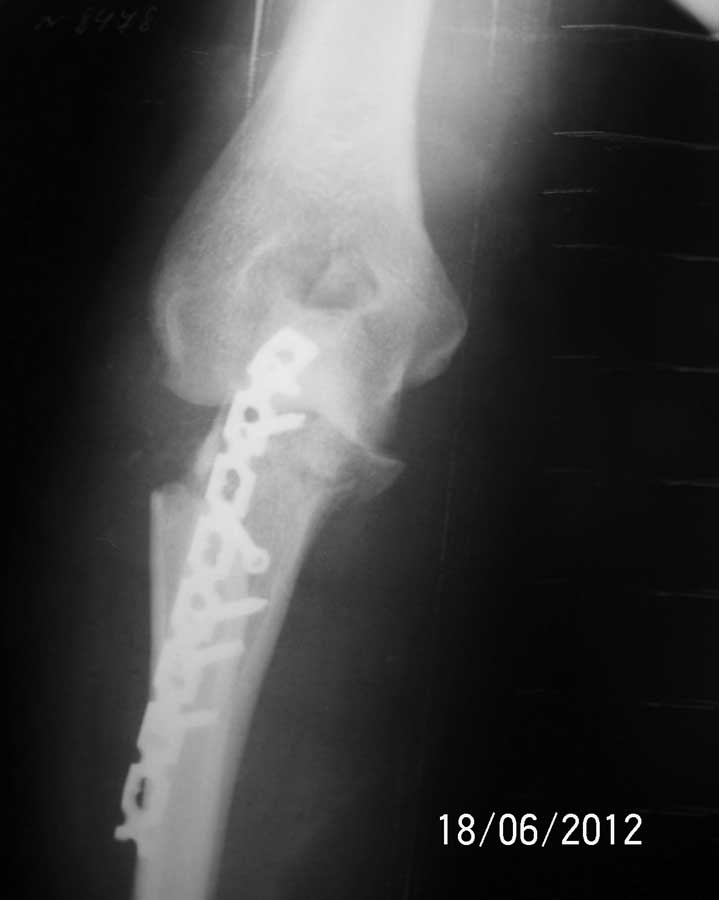

Операция состоялась. Выполнить остеосинтез головки лучевой кости не удалось из-за оскольчатого характера перелома. Её пришлось резецировать. Произведен остеосинтез проксимального отдела локтевой кости LCP реконструктивной пластиной.

Рентгенограммы прилагаются.